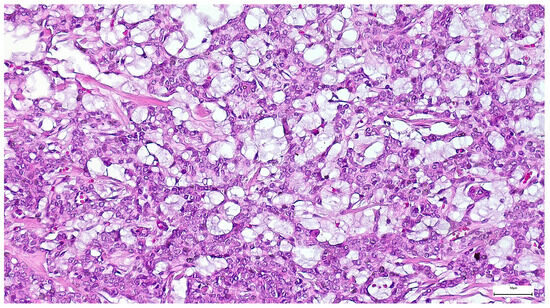

Among Warthin tumor histological subtypes, the infarcted/metaplastic variant was recorded in 18 cases (14.88%), while the common subtype has been identified in 103 cases (85.12%) (Table 3). Grossly, these appeared as well circumscribed masses, of 11–85 mm diameter, with solid areas, multiple cysts, and papillary projections on the cut section. The lesions exhibited a microscopic papillary-cystic proliferation, lined by a bilayered oncocytic epithelium, associated with a prominent lymphoid stroma (Figure 11). Additional morphologic changes included ischemic-type necrosis, along with squamous metaplasia (15 cases; 12.39%), and mucinous metaplasia (one case; 0.82%). Considering that their diagnosis was straightforward, an IHC investigation was not required.

Figure 11. Warthin tumor showing a bilayered oncocytic epithelium with prominent papillary infoldings and a dense lymphoid stroma (H&E staining, 20×).